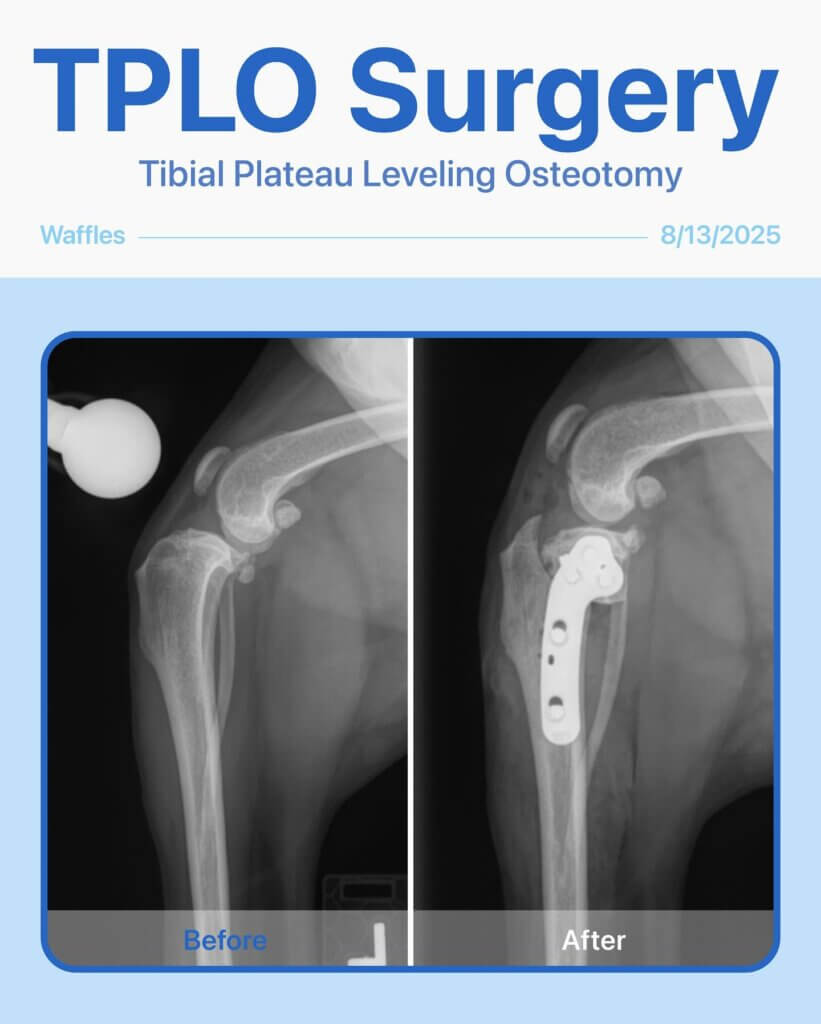

Before & After – TPLO Surgery for Waffle!

Waffle, our sweet 4-year-old girl, came in with a limp in her back left leg and low energy that had been bothering her for a few months. After a thorough physical exam and radiographs, we diagnosed her with a cranial cruciate ligament (CCL) rupture—a common injury in dogs that causes pain, instability, and difficulty walking.

To restore her mobility and relieve pain, Waffle underwent TPLO (Tibial Plateau Leveling Osteotomy) surgery. The procedure went smoothly, and Waffle is on her way to a full recovery!